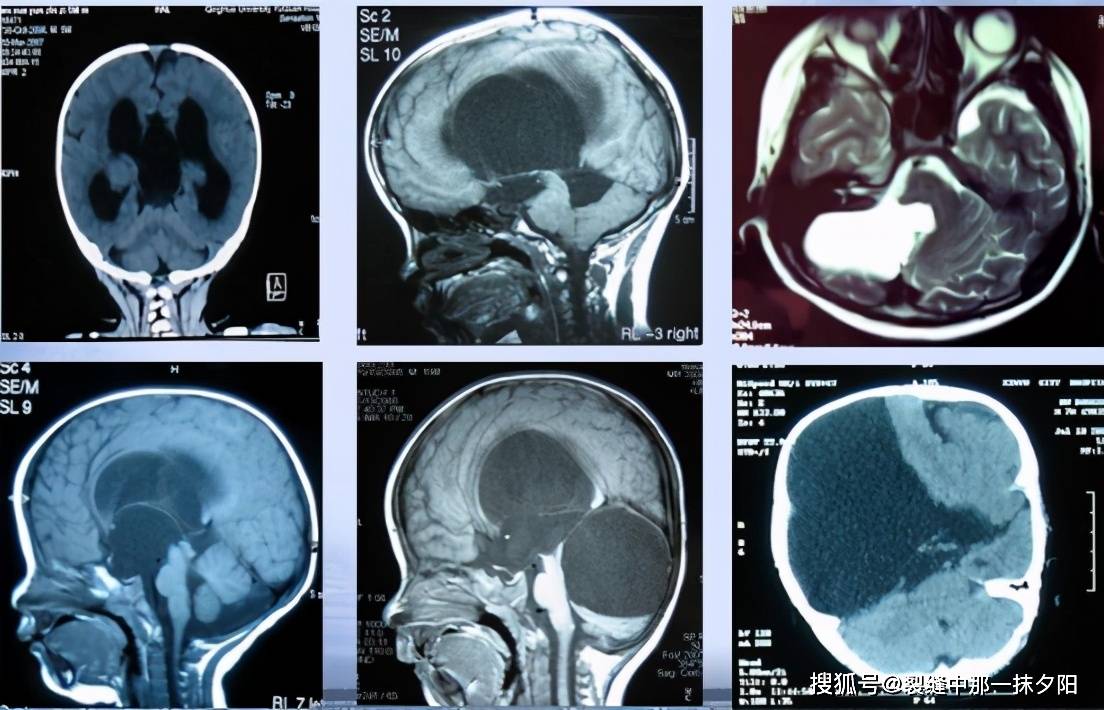

原创贺晓生教授儿童颅内巨大蛛网膜囊肿手术治疗案例

贺晓生教授儿童颅内巨大蛛网膜囊肿手术治疗案例 - 好大夫在线

什么是颅内蛛网膜囊肿,该如何治疗? - 好大夫在线

贺晓生教授儿童颅内巨大蛛网膜囊肿手术治疗案例